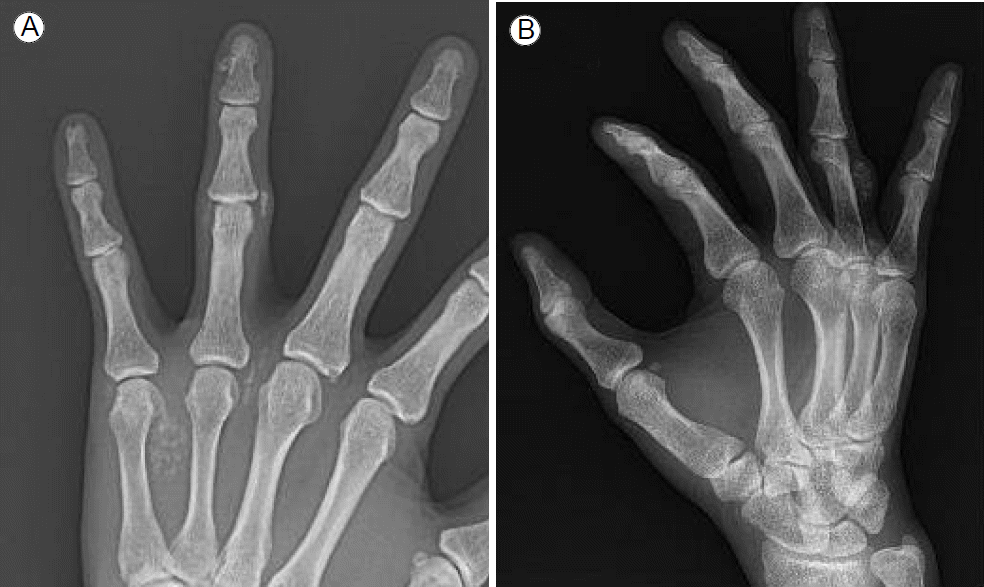

임상 경과 및 치료: 외래에서 고요산혈증(uric acid 7.6-9.2 mg/dL)으로 아침에 한 번 allopurinol 50 mg을 2년 정도 지속적으로 복용해 오던 중이었음에도 불구하고 내원 시 both hands x-ray상 연조직부 tophi 확인되어 다음 날 excisional biopsy 수술이 진행되었다(Fig. 1). 술 후 증량된 allopurinol 100 mg을 하루 한 번 복용하였으나 3개월 뒤 다시 결정성 통풍이 재발하여 2차 제거 수술을 하고, 수술 후 1일차부터 febuxostat 40 mg 경구 1회 요법을 시작하였다. 복용 시작 후 3개월 뒤 혈청생화학 검사결과 BUN 62.8 mg/dL, 크레아티닌 15.9 mg/dL, 나트륨 134 mM/L, 칼륨 4.8 mM/L, 총 단백 5.6 g/dL, 알부민 3.8 g/dL, AST 17 IU/L, ALT 11 IU/L, ALP 178 U/L, 혈청요산 농도가 5.9 mg/dL까지 감소하였고 지속적으로 febuxostat 40 mg 하루 한 번 복용을 유지해 20개월이 지난 현재까지 재발을 보이지 않았다(Fig. 2).

Figure 1.

Both hands showed evidence of chronic tophaceous gout, with tophi on the (A) left fourth finger and (B) right thumb and wrist.